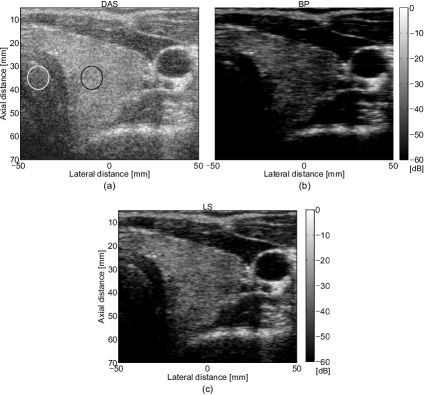

Figure 11: (a) DAS, (b) BP, and (c) LS BF results of in vivo thyroid data with tumor.

TABLE VI: CNR, SNR, and RG values for the in vivo thyroidal beamformed images from Fig. 11

BF Method CNR SNR RG

DAS 0.71 0.62 1

BP 1.16 0.79 2.9

LS 1.32 0.86 1.5

The beamformed results of the thyroid data with tumor are presented in the Fig. 11. The malignant tumor with an irregular structure can be seen between the left lobe of the thyroid (the hyper-echoic structure situated near the trachea) and the carotid artery (the hypo-echoic circular structure with the center at approximately 33 mm (axially) and 40 mm (laterally). We can observe that, contrarily to DAS beamformed image, where the tumor is hard to be distinguished (see Fig. 11 (a)), both our methods improve the visualization of the main structures, enhancing the edges of the tumor. The values of CNR, SNR, and RG are depicted in the Table VI, where a gain in resolution with a factor of almost 3 can be observed when using BP, compared with DAS, while with LS we obtain a higher improvement in contrast and SNR than with BP BF. CNR was computed by considering region R2subscript𝑅2R_{2} inside the tumor (the black circle positioned at 00 mm laterally), and the region R1subscript𝑅1R_{1} inside the left lobe of the thyroid (the white circle positioned at approximately 2020-20 mm laterally). The SNR for R1subscript𝑅1R_{1} was computed.